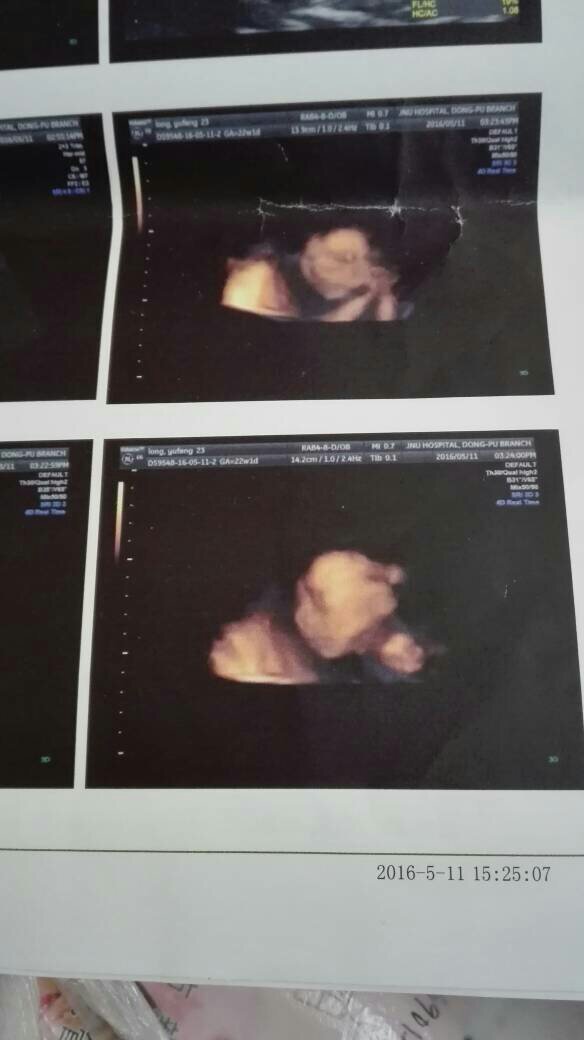

去照了4维,小宝宝脑袋下面蓝色的是什么 点击展开 匿名用户 2016-05-13 14:10 满意回答 您好!结果没有报出胎儿有什么异常,就勒搂没关系,以上只是照裕导片,蓝色可能是血北搁训管! fang 2016-05-13 15:01 宝宝知道提示您:回答为网友贡献,仅供参考。 相关问题 有些小宝宝的眼珠是淡蓝色的是怎么回事? 养一个小宝宝 有粉色或蓝色的 这个游戏叫什么 仓鼠,你们说买哪个,大一点的(蓝色)只是增加了二十块钱…主要是想以后仓鼠生小宝宝哪个好